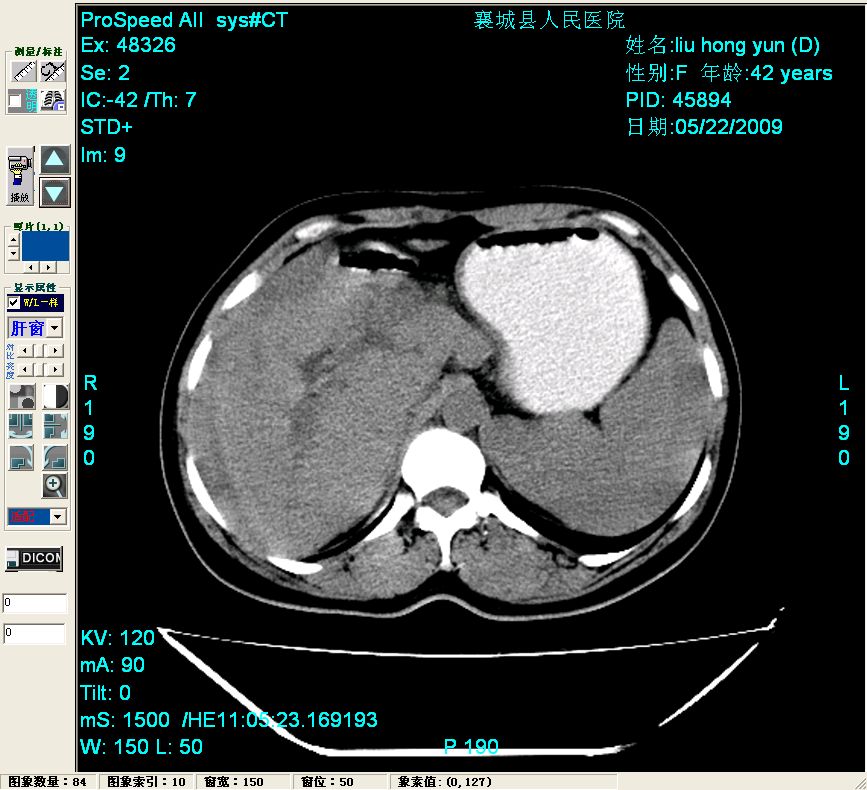

平扫:

平扫左肝外叶体积显著减小,左肝外叶见多房囊性低密度区,左肝实质及右肝前叶浅表实质呈低密度改变,左肝及右肝前叶胆管扩张,脾大